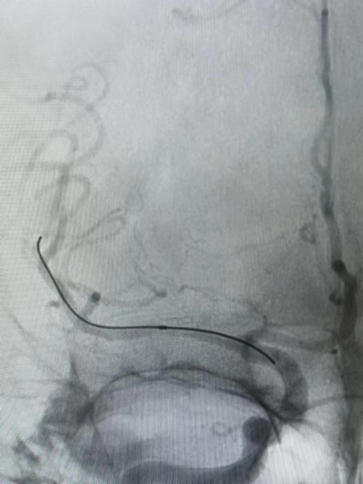

Guiding到位,导丝通过病变。

导丝怎么扩【载药时代 球扩天下】NOVA DES®颅内药物洗脱支架在大脑中动脉重度狭窄的应用二例!_https://www.jmylbn.com_新闻资讯_第24张

球囊通过病变。

导丝怎么扩【载药时代 球扩天下】NOVA DES®颅内药物洗脱支架在大脑中动脉重度狭窄的应用二例!_https://www.jmylbn.com_新闻资讯_第25张